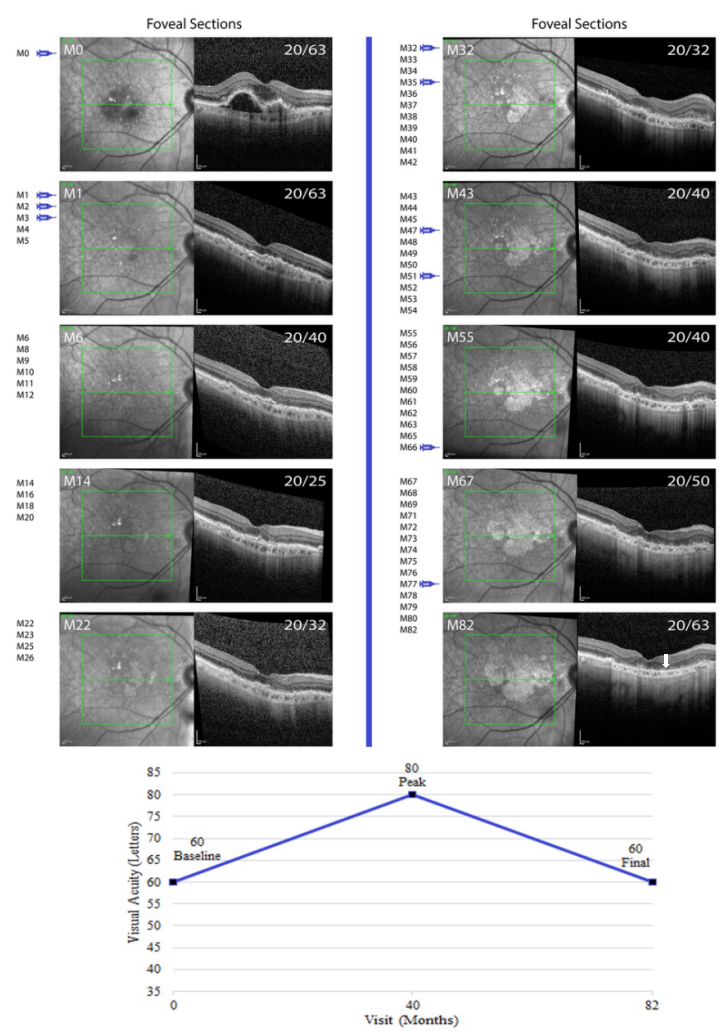

The median time from treatment initiation to development of macular atrophy was 29.6 (IQR, 17.7 - 43.4) months (Table 1). Of the 47 eyes, 7 (14.9%) developed new-onset atrophy by the end of year 1, 12 (25.5%) during year 2, 11 (23.4%) during year 3 and 11 (23.4%) during year 4. The remaining 6 eyes developed atrophy after 4 years of follow-up.Three situations predisposing to macular atrophy were identified: collapse of a vascularized PED, development of SRHRM and/or subretinal fibrosis, or in association with large drusen and pigmentary changes resulting in an arc of atrophy partially surrounding the fovea in a pattern typically referred to as geographic atrophy (Table 1). Vascularized PEDs with leaking type 1 CNV based upon the presence of overlying subretinal or intraretinal fluid were common in this population of eyes with NVAMD that developed macular atrophy. In 25 eyes, the vascularized PED collapsed during the course of anti-VEGF treatment and after PED collapse, RPE and outer retinal atrophy was observed in that location (Table 1). In 15 of the 25 eyes (60.0%), subretinal and/or intraretinal fluid was reduced and the need for anti-VEGF injections was lessened after PED collapse/atrophy onset, suggesting CNV regression. Figure 1 shows IR images and SD-OCT scans through the fovea of a subject who had collapse of a vascularized PED, onset of atrophy, and reduced vision 43 months after the last anti-VEGF injection. This subject had mild subretinal fluid that resolved after 4 anti-VEGF injections and then maintained good vision without treatment until month (M) 49 when the PED under the fovea collapsed and atrophy became evident. Figure 2 shows images from a subject who had collapse of a vascularized PED and early signs of mild atrophy within 1 month of the first antiVEGF injection. The central atrophy gradually worsened even during a long period without anti-VEGF injections. The patient developed a small PED inferior to the fovea that collapsed by M37 after which there was progressive atrophy in that location as well. Figure 3 shows images of a patient who had collapse of a vascularized PED beneath the fovea after 2 anti-VEGF injections with partial recurrence during 2 months without treatment. During and after treatment with 5 additional anti-VEGF injections, the PED and all intraretinal fluid resolved and there was progressively worsening atrophy involving the fovea with reduction in vision.

Figure 1 Development of macular atrophy following collapse of a vascularized pigment epithelial detachment 43 months after the last anti-VEGF injection.

Figure 3 Macular atrophy after collapse of a vascularized pigment epithelial detachment, partial recurrence, and then resolution.

Visual Outcomes

The median VA at last follow up was 55 (IQR, 35 - 70) letters, a median loss of 10 letters (Supplemental Table 2). However, the median peak VA was 75 (IQR, 70 - 80) indicating that on average, subjects gained 10 letters and then subsequently lost 20 letters, a large swing in VA. The median time from baseline to last peak vision was 24 months indicating that most subjects maintained their best vision for about 2 years. Final VA was ≥20/50 in 36.2%, 20/63-20/160 in 34.0%, and ≤20/200 in 29.8%, while peak vision was ≥20/50 in 91.5%, 20/63-20/160 in 8.5%, and ≤20/200 in 0%. Subjects were classified as good visual outcome if final VA was ≥20/50, moderate outcome if VA was 20/63-20/160, and poor outcome if VA was ≤20/200. The pattern of initial gain and subsequent loss of vision occurred across all 3 outcome groups, with the major difference being the amount of loss occurring after initial gain (Supplemental Figure 4). The median number of anti-VEGF injections was 20, but this is not very informative because of the differences in follow-up duration. The injection frequency is more informative; 14.9% received injections every 4-6 weeks, 31.9% received relatively frequent injections (usually between 6 and 12 weeks apart in a treat-and-extend or frequent prn regimen), and 53.2% received prn treatment with relatively long intervals between injections. At last follow-up, atrophy involved the fovea in 44.7% and was felt to contribute to reduced vision, while in 55.3% atrophy was non-fovea involving and did not contribute to reduced vision. In 36.2% of subjects, subretinal fibrosis was present in association with atrophy at last follow-up.DISCUSSION